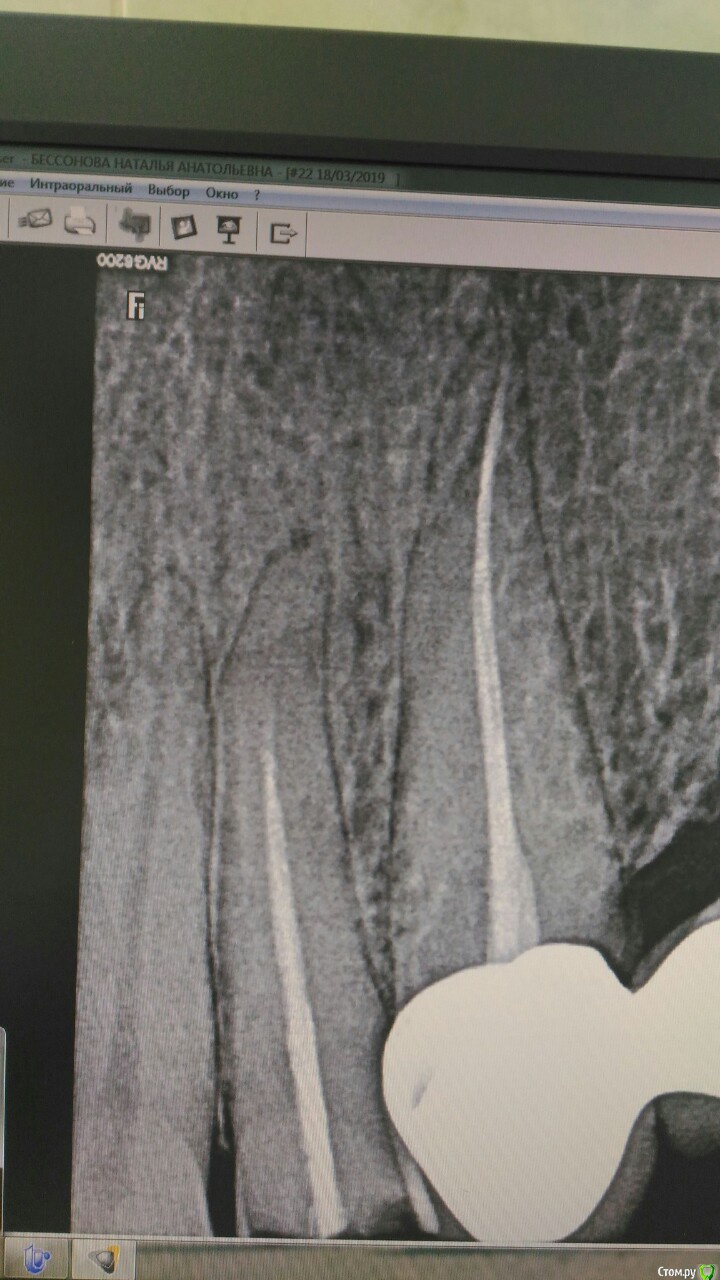

Кларита Опубликовано 18 марта, 2019 Поделиться Опубликовано 18 марта, 2019 Ситуация следующая: пацинетку направили из другой клиники к ортопеду,(22 расцементировка мк коронки с отломо культи 22 зуба, расцементировка мк моста 23-26(26-корни, мост давно носится пацинкой на Кореге, 27-хр.периодонтит под металлической коронкой.22 похоже предыдущий оператор перфорировал и с формулировкой -распломбировать с/в штифт не удалось-направил ко мне).Ситуация осложняется тем, что отлом 22 зуба произошел после удара и пациентка собирается на обидчика в суд подавать. От КЛКТ отказалась-дорого(со слов направившего коллеги).Вопрос-что бы вы делали на месте ортопеда ? как правильно описать карту? или отправить от греха подальше? Ссылка на комментарий